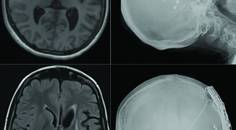

Evaluation revealed a relatively low opening cerebrospinal fluid (CSF) pressure (80 mm of water), lower cranial nerve palsies, and ataxia. Contrast-enhanced MRI of the brain and spine demonstrated brainstem sagging with significantly decreased mamillopontine distance (3 mm), tonsillar herniation, and mild pachymeningeal enhancement of cerebral convexities (Figure 1, A and C), without any spinal longitudinal epidural collection (Figure 1B). To rule out any spinal longitudinal epidural collection and negative spontaneous intracranial hypotension (SIH), a dynamic prone CT myelogram (CTM) was performed but failed to demonstrate a CSF leak or delayed contrast excretion in the renal pelvis. Therefore, dynamic digital subtraction myelography (DSM) in the right followed by left lateral decubitus positions was also performed, but the results were unremarkable (Figure 1, D and E).

Figure 1. Sagittal 3-dimensional fluid-attenuated inversion recovery MRI scan shows evidence of brainstem sagging with tonsillar herniation (white arrow) and a reduced mammillopontine distance (broken white arrow), consistent with spontaneous intracranial hypotension (A). Spinal MRI screening shows no evidence of spinal longitudinal extradural cerebrospinal fluid (CSF) collection (B). Axial contrast-enhanced T1 MRI scan shows postcranioplasty changes with diffuse dural thickening and enhancement (C). Lateral decubitus digital subtraction myelography of the left (D) and right (E) sides shows no obvious CSF leak or CSF–venous fistula. Axial CT scan of the head shows a cement cranioplasty graft with improper opposition (white asterisks) (F).